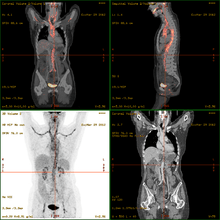

- 18F-fluorodeoxyglucose positron emission tomography/computed tomography (FDG-PET/CT)has become a widely used imaging tool in patients with suspected Large Vessel Vasculitis, due to the enhanced glucose metabolism of inflamed vessel walls.[9] The combined evaluation of the intensity and the extension of FDG vessel uptake at diagnosis can predict the clinical course of the disease, separating patients with favourable or complicated progress.[10]